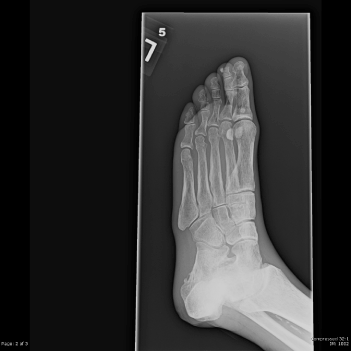

Laboratories showed a white blood count (WBC) of 1900/mm3, with 15% neutrophils, 82% lymphocytes, and 3% monocytes. The hemoglobin was 9.7 gm/dl and the platelet count was 191,000/mm3. An echocardiogram demonstrated moderate aortic stenosis. Plain films of the foot demonstrated osteosclerosis and soft tissue calcifications (Figure 1). Osteomyelitis was noted on an MRI of the left foot.

Figure 1. Plain film of the foot demonstrates diffuse osteopenia, osteosclerosis and soft tissue calcifications